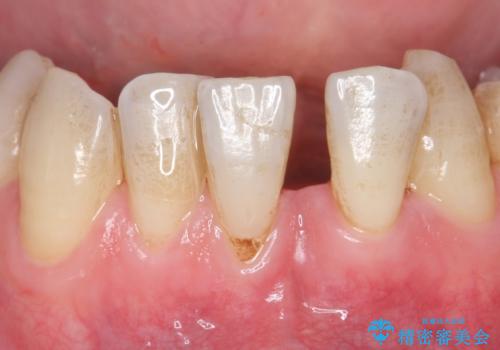

30代女性 ミゼラブルな前歯の陥没を再生する①1次手術による骨造成

- 治療計画

- 他院にて前歯を抜歯され、その後の組織の吸収によりシビアな欠損を伴う状態であった

→2度の手術により失われた骨・および軟組織の再生を図り、最終的にセラミックにて修復を終えた

1次骨造成

1次手術は大きく失われた骨の回復をイニシアティブとして行いました。チタンメッシュは露出や撤去必須などのデメリットがありますが、大規模な骨造成においてはハウジングという観点で圧倒的な安心感があります。

少しでも多くボリュームを増やすことと、骨造成部位の保護という意味で、メッシュとメンブレンを、さらに結合組織で覆うという術式をとりました。単純に結合組織を持ってくると血流の条件を難しくしてしまうため、組織を完全に切り離さず、有茎弁の状態で翻転させ移植しています。